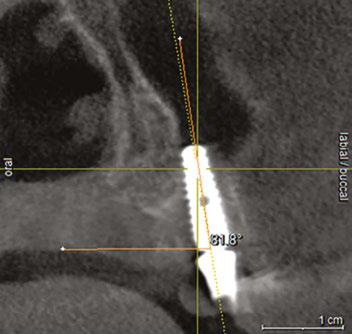

Let’s review a recent case that showcases the rationale and techniques of the top three. It is common to utilize several suturing techniques in surgical closure, especially in larger grafting cases. In the following case, a lateral sinus lift was performed, and all three techniques were used to their full effect. Simple interrupted sutures are used to close small incisions and place tissue margins accurately back in place; horizontal mattress sutures are used to hold membranes in place and relieve tension over the incision line, and running interlocking continuous sutures are used to close longer incisions with watertight closure for maximum healing potential via primary closure.

A patient presented with a failing bridge on the upper left that is supported by three mini implants. The implants directly perforate the sinus and only ~2mm of residual bone height remains on the crest (Figure 8). The mini implants were removed, and a

Figures 7A and 7B: Horizontal mattress sutures are useful for helping to secure membranes in grafting situations and relieving tension in longer span incisions Figures 8A and 8B: The pre-op condition of the patient with mini implants engaging minimal bone and perforating the sinus. The patient’s implant supported bridge was loose and causing discomfort Figure 9: A periosteal biting mattress engages only the periosteum in the buccal vestibule and exit and re-enters on the lingual tissue, helping to secure the membrane tightly over the window and crest